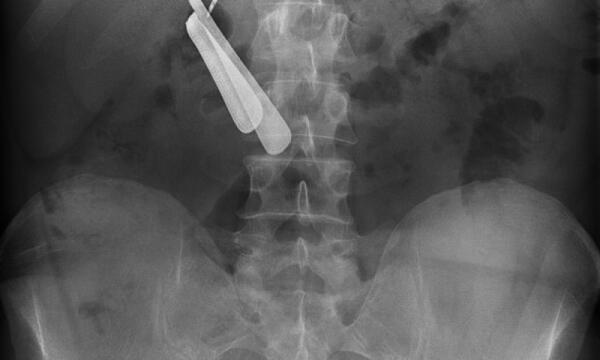

Punte di trapano, batterie e una forchetta nello stomaco: operato d’urgenza all’Icot di Latina. Ora sta bene